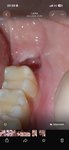

Pretrvávajúca bolesť po extrakcii dolnej osmičky

Dobry den, prosim o rady, pomoc. Som 13 dni po extrakcii dolnej osmicky. Nekomplikovanej ale zubarka povedala ze korene boli dost hlboke. Prve dva dni boli v poriadku, treti prisli mierne bolesti. Bra